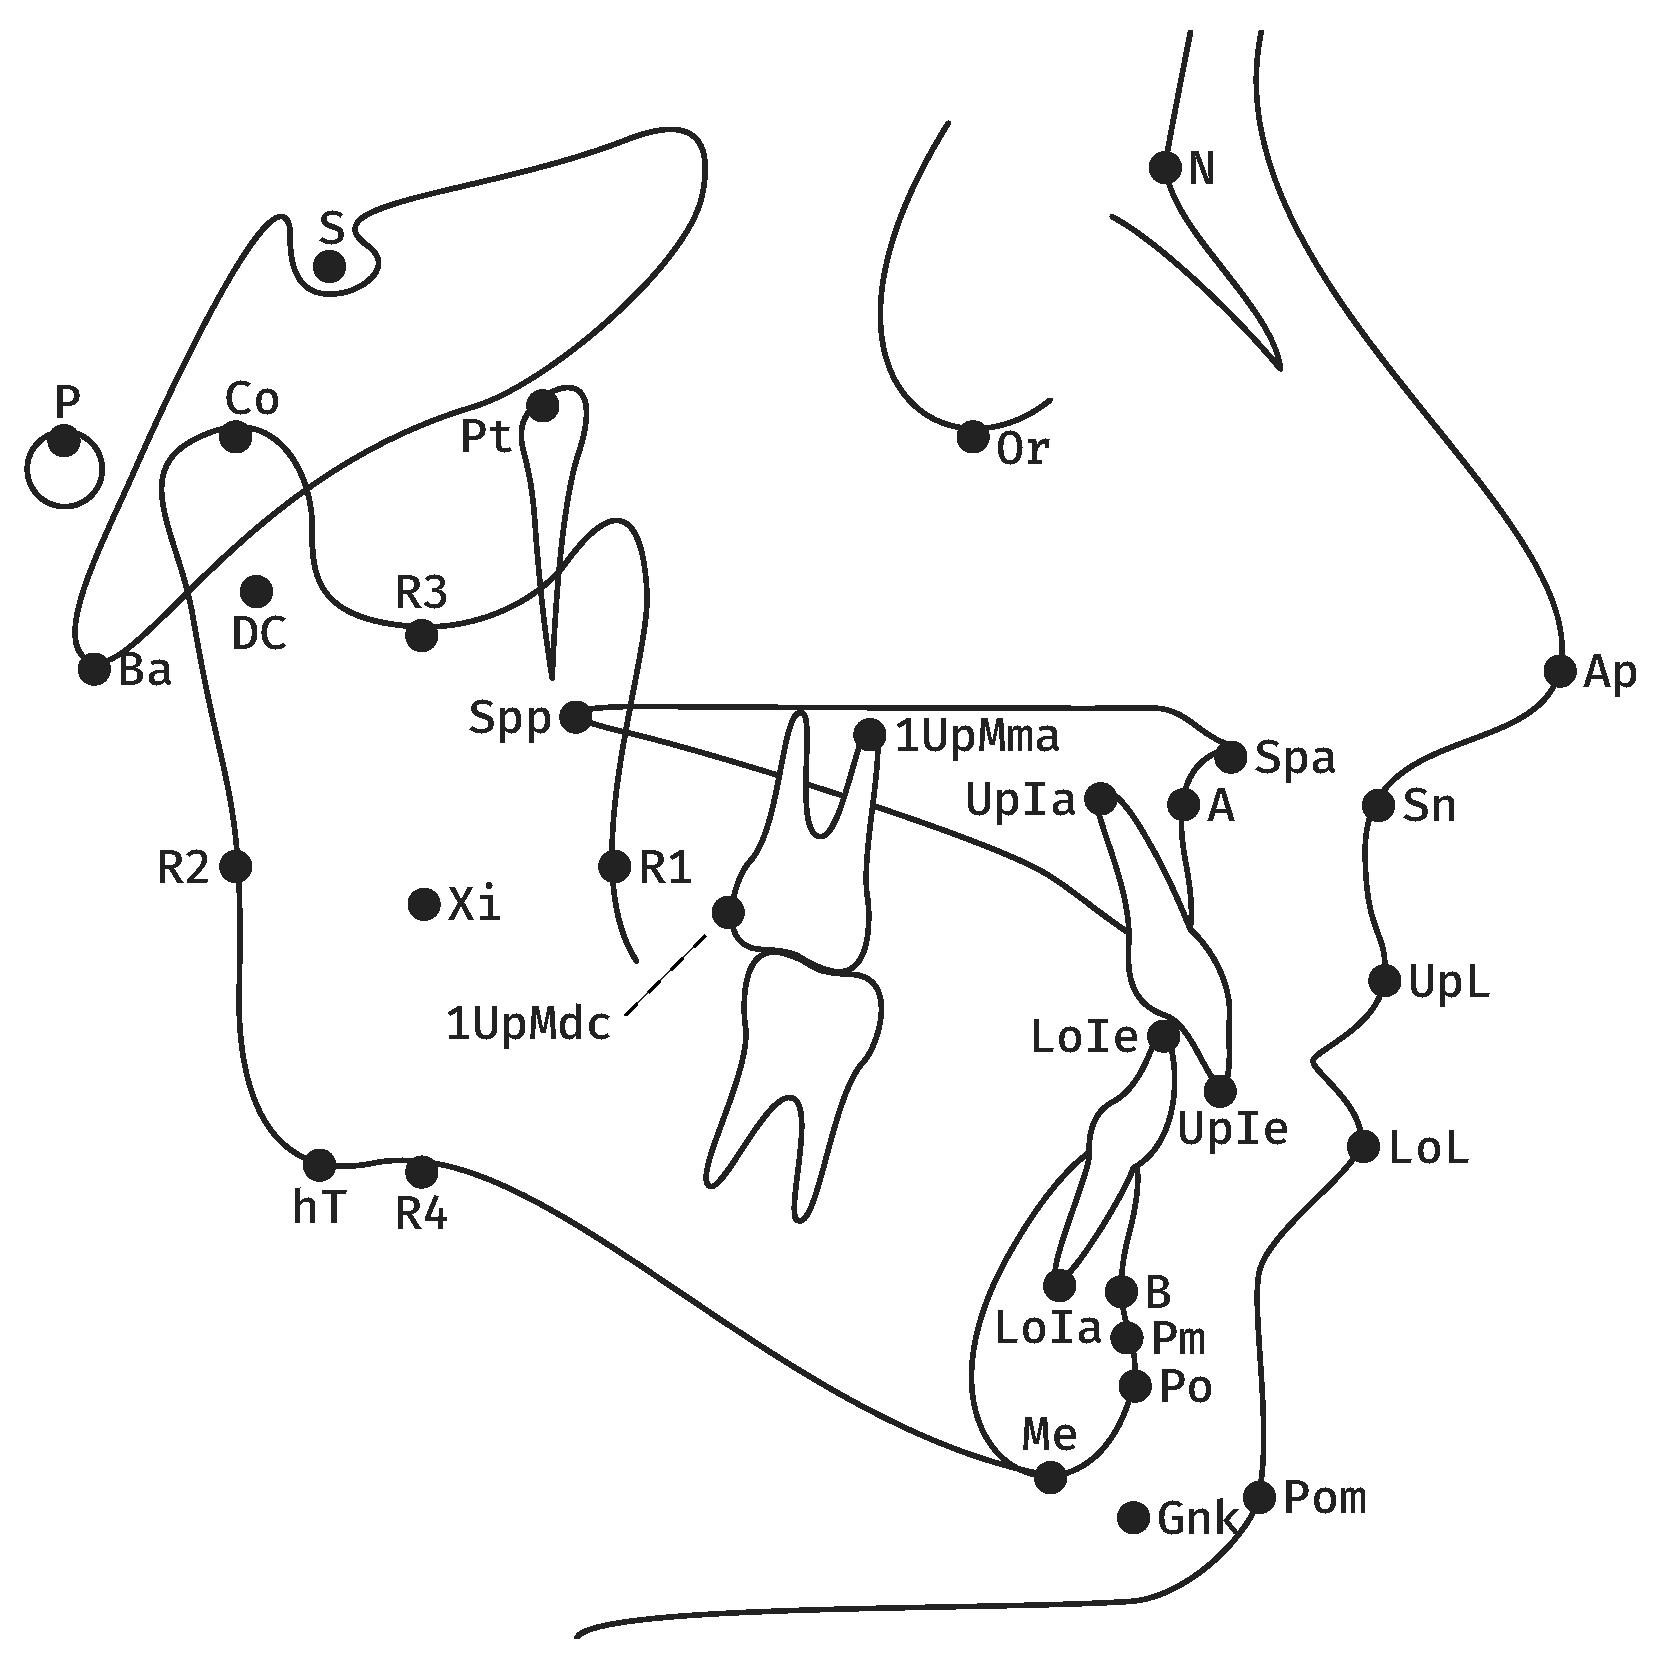

2. Materials and Methods

| Measurement | Definition | |

|---|---|---|

| 1 | Facial axis | Posterior angle btw. Ba-N and Pt-GnK. |

| 2 | Facial depth | Posterior angle btw. P-Or and N-Po. |

| 3 | SNB | Posterior lower angle btw. S-N and N-B. |

| 4 | Mandibular plane | Anterior angle btw. P-Or and hT-Me. |

| 5 | Inner gonion angle | Anterior angle btw. DC-Xi and Xi-Pm. |

| 6 | Relative mandibular length | Length of Co-Po. |

| 7 | Maxillary position | Posterior lower angle btw. Ba-N and N-A. |

| 8 | SNA | Posterior lower angle btw. S-N and N-A. |

| 9 | Palatal plane | Anterior angle btw. P-Or and Spa-Spp. |

| 10 | Rel. max. length | Length of Co-A. |

| 11 | Lower facial height | Anterior angle btw. Spa-Xi and Xi-Pm. |

| 12 | Convexity of point A | Distance btw. A and N-Po. |

| 13 | Rel. max. to mand. length | Ratio btw. Co-A and Co-Po. |

| 14 | Lower Incisor position | Distance btw. LoIe and A-Po. |

| 15 | Lower Incisor inclination | Caudal angle btw. LoIe-LoIa and A-Po. |

| 16 | Upper Incisor position | Distance btw. UpIe and A-Po. |

| 17 | Upper Incisor inclination | Caudal angle btw. UpIe-UpIa and A-Po. |

| 18 | Inter-Incisor angle | Anterior angle btw. UpIe-UpIa and LoIe-LoIa. |

| 19 | Vertical molar distance | Distance btw. 1UpMma and Spa-Spp. |

| 20 | Sagittal molar distance | Distance btw. 1UpMdc and a vertical to P-Or from Pt. |

| 21 | Lower Lip to E-Line | Distance btw. LoL and Ap-Pom. |

| 22 | Upper Lip Drape | Posterior angle btw. UpL-Sn and P-Or. |